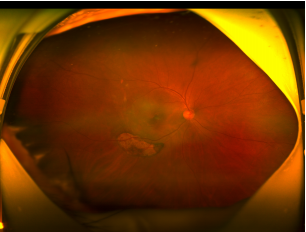

今年 6 月份,62 岁的周先生无明显诱因下出现右眼视力下降,便来到柳州市红十字会医院就诊,检查发现他的右眼玻璃体积血、右眼息肉样脉络膜血管病变。

考虑到周先生出血面积较大,发病时间相对较短,眼底病团队与他本人及家属充分沟通后,眼三病区主任黄红波和副主任韩光杰为其加急实施了手术,术中切除玻璃体后,采用 41 G 超精微针把 t-PA 注射到黄斑下血凝块内,促使血凝块溶解,促进吸收。

术后一周,黄斑部的积血基本吸收,重现黄斑结构。为了稳定周先生的病情,预防再次出血,眼底病团队计划根据眼底复查情况再决定是否规范化的抗 VEGF 药物眼内注射治疗。